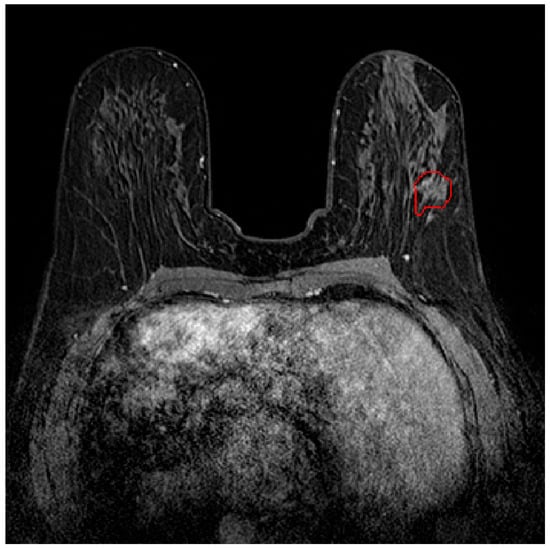

Radiomics and Machine Learning Approaches for the Preoperative Classification of In Situ vs. Invasive Breast Cancer Using Dynamic Contrast-Enhanced Magnetic Resonance Imaging (DCE–MRI)

2.1. Dataset